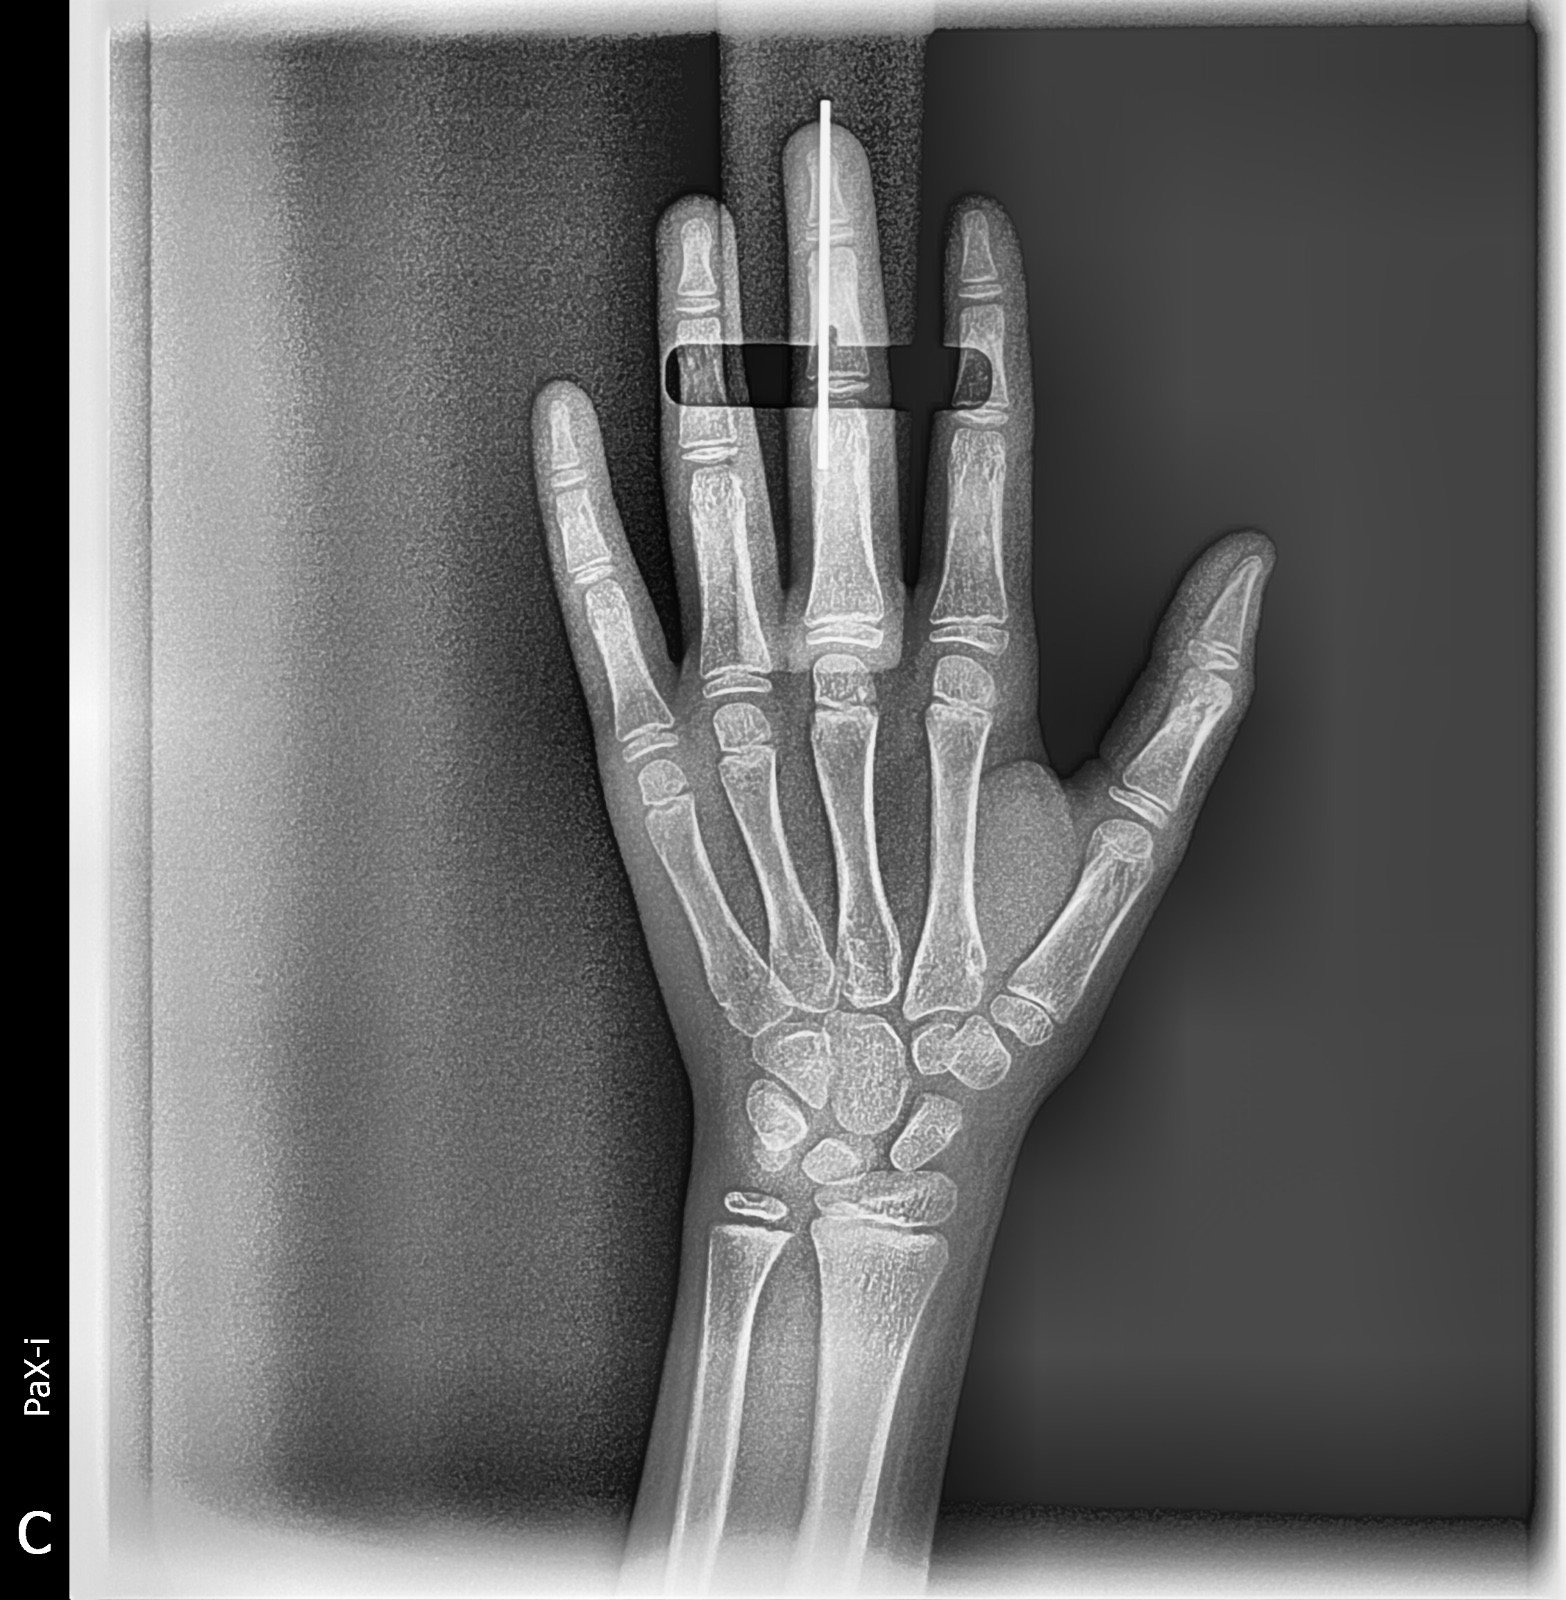

Imagen de Rx Carpal

Rx Carpal

Rx Carpal 🤚 se utiliza para revisar los huesos de la muñeca (carpiano,radio,cúbito) detectar fracturas,luxiones o esguinces. evaluar artrosis, artritis u otras alteraciones articulares. medir la edad ósea en los niños y adolescentes

Costo: Consultar precio Duración: 10 min